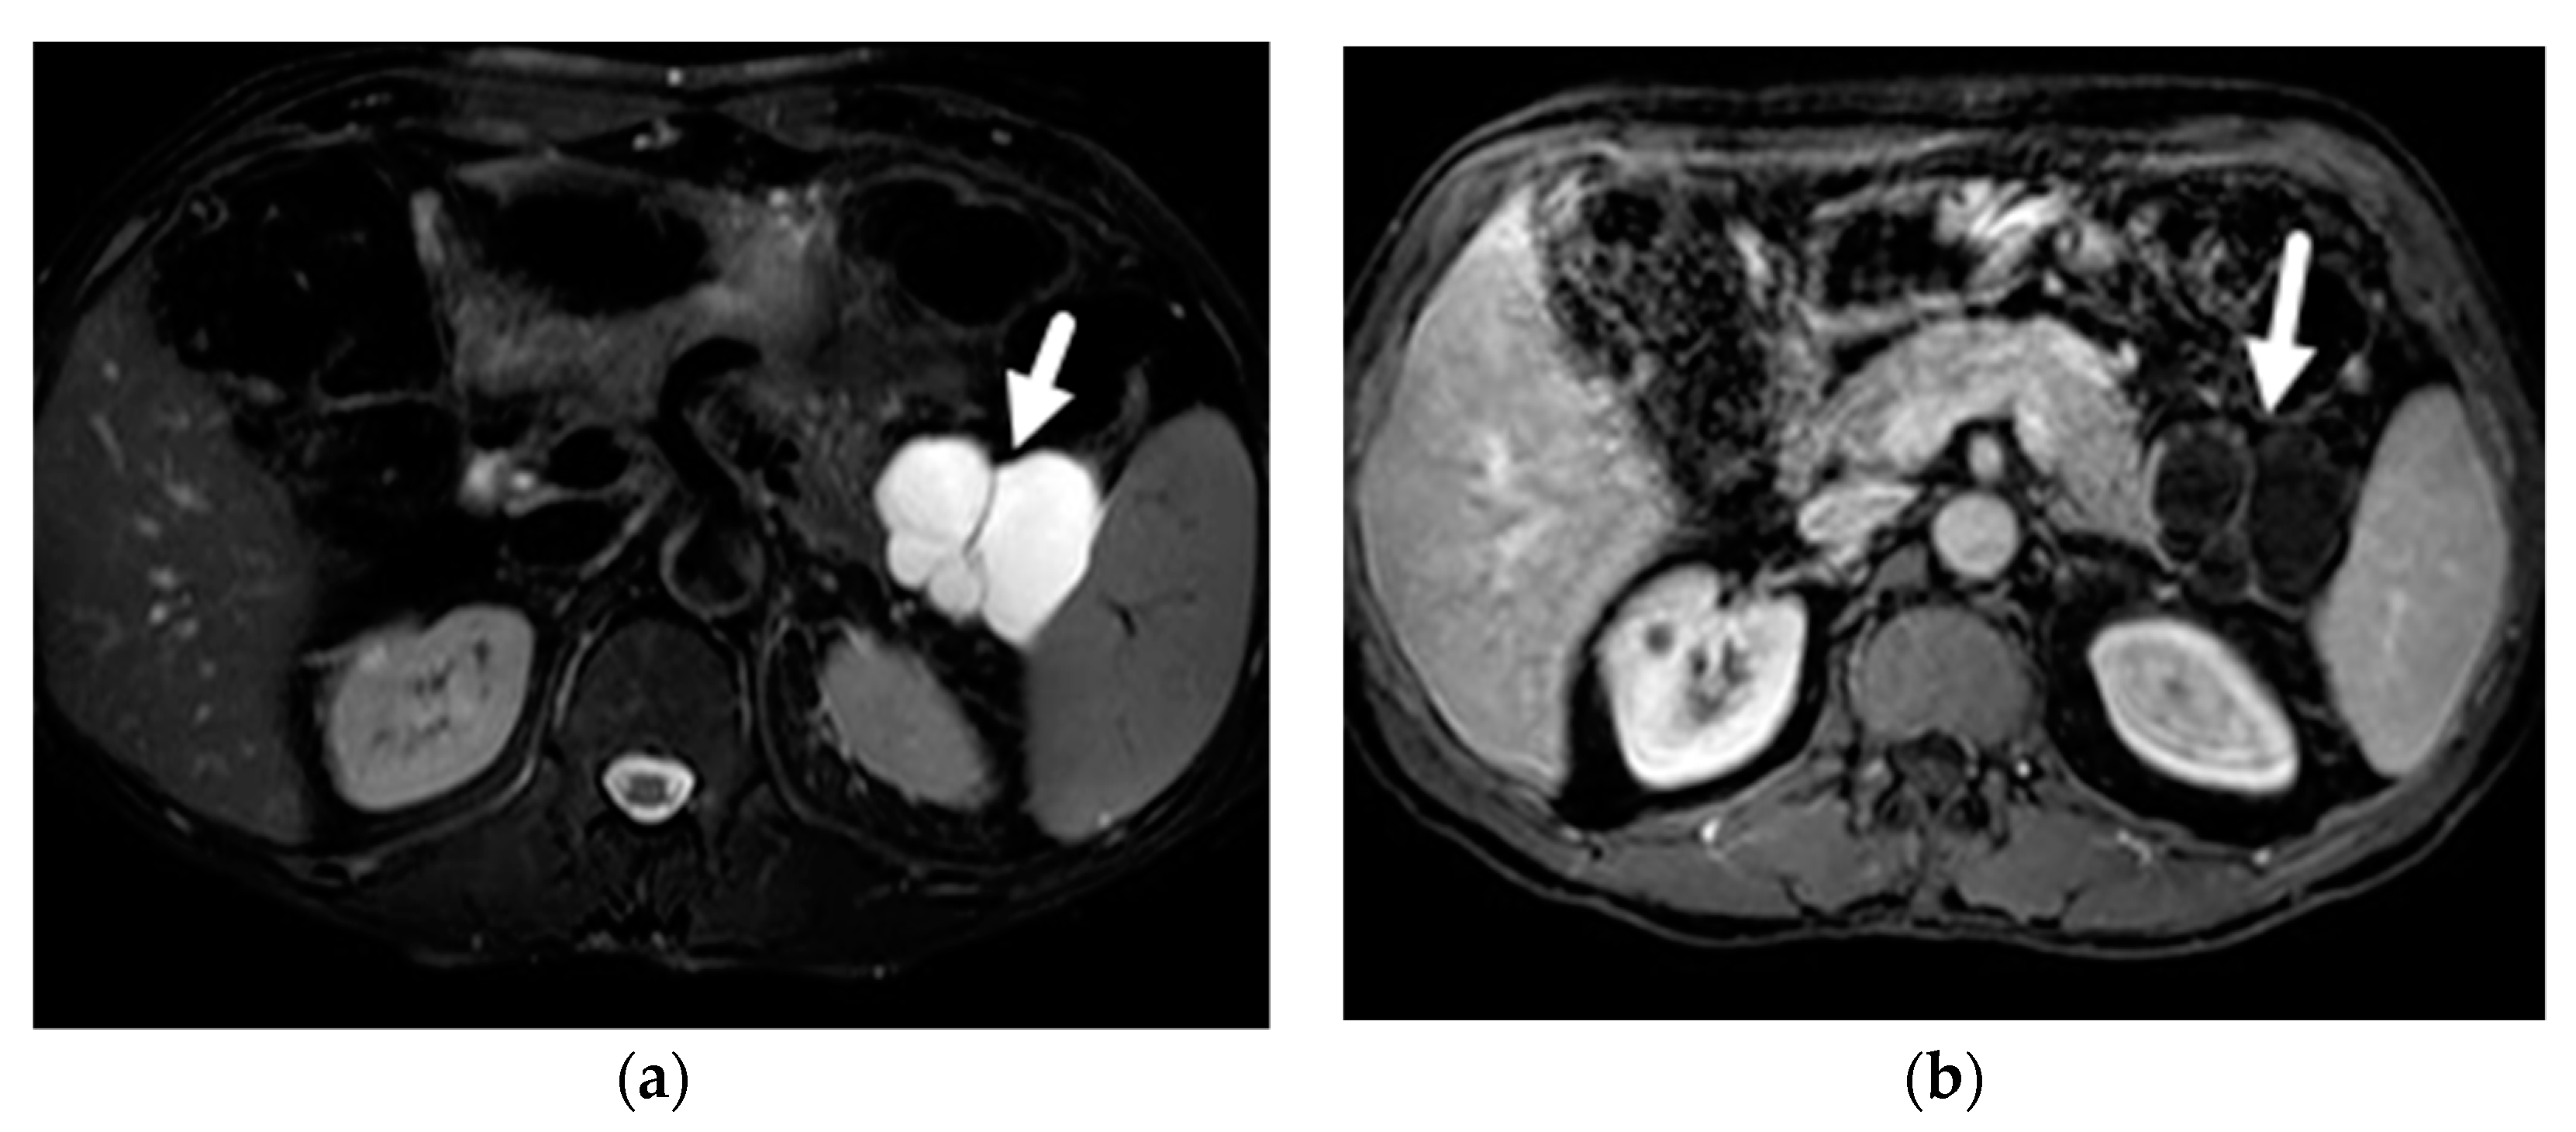

- Macari, M.; Finn, M.E.; Bennett, G.L.; Cho, K.C.; Newman, E.; Hajdu, C.H.; Babb, J.S. Differentiating pancreatic cystic neoplasms from pancreatic pseudocysts at MR imaging: Value of perceived internal debris. Radiology 2009, 251, 77–84. [Google Scholar] [CrossRef]

- Tirkes, T.; Aisen, A.M.; Cramer, H.M.; Zyromski, N.J.; Sandrasegaran, K.; Akisik, F. Cystic neoplasms of the pancreas; findings on magnetic resonance imaging with pathological, surgical, and clinical correlation. Abdom. Imaging 2014, 39, 1088–1101. [Google Scholar] [CrossRef] [PubMed]